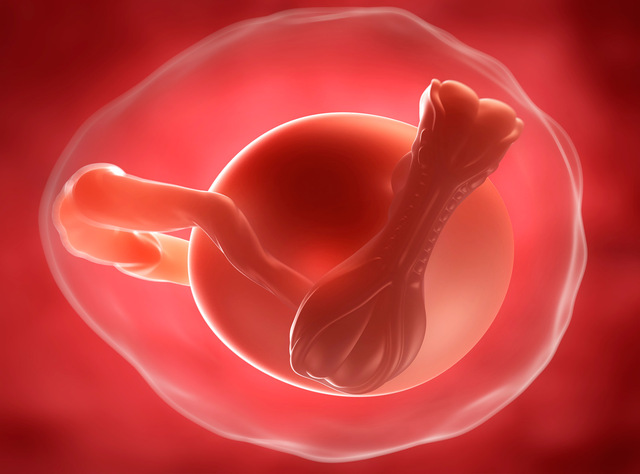

Segunda etapa

El embrión constituye esta etapa. Comienza cuando se logra la implantación en el útero. Abarca desde la tercera semana a la novena